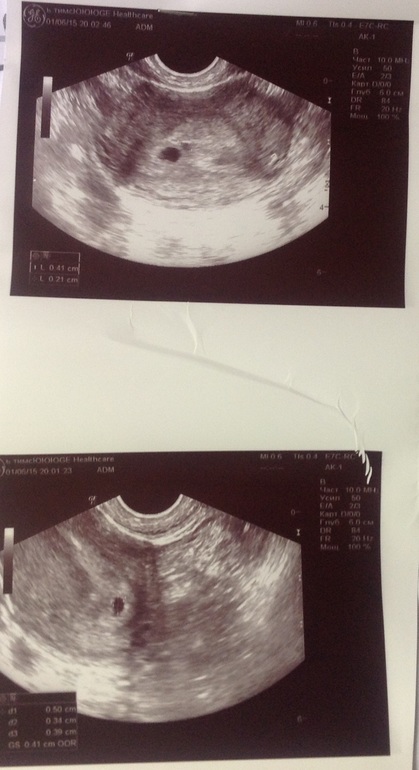

d8547ba367eb11cdffc44dddbcd94149.jpg

e917c9eae8f913c6ac40f5819bb94687.jpg